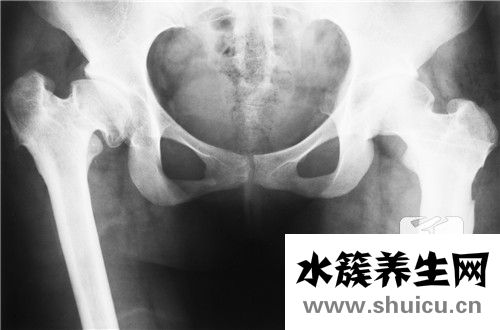

骨盆是我們?nèi)梭w的關(guān)鍵部位。有些人經(jīng)常感到骨盆疼痛,尤其是當(dāng)他們站起來或坐下時。這種情況主要是由于骨盆肌肉勞損或者過度運(yùn)動導(dǎo)致的乳酸菌過多。這種乳酸菌還沒有被消耗掉,人體已經(jīng)造成了過度積...